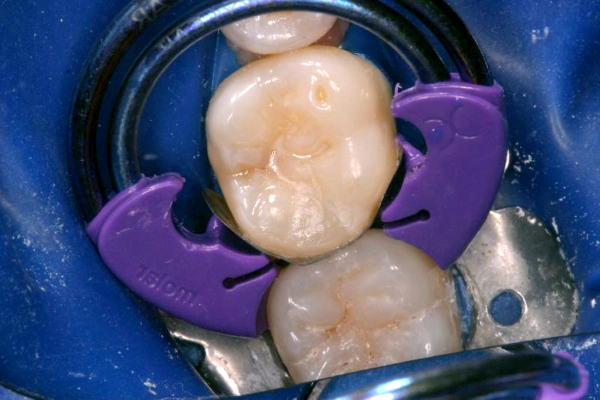

Click on an image below to enlarge & view caption.

Dentistry and photography courtesy of Dr. Robert Margeas.